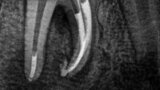

Fig. 2a: Conventional radiograph of an endodontically treated tooth #11 and cold-sensitive tooth #12 compared with CBCT imaging showing the presence of a large apical bone defect (taken at a two-day interval).

Fig. 2b: Conventional radiograph of an endodontically treated tooth #11 and cold-sensitive tooth #12 compared with CBCT imaging showing the presence of a large apical bone defect (taken at a two-day interval).